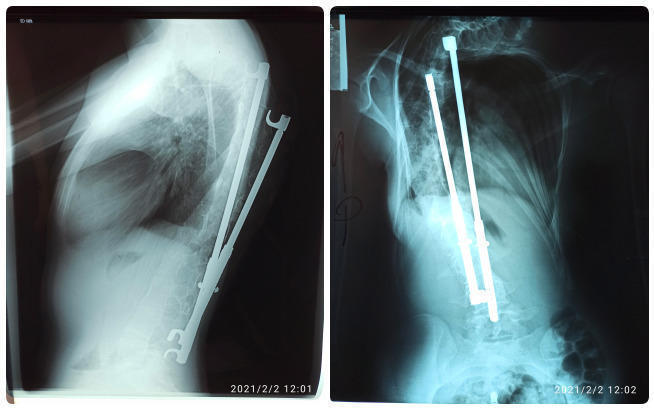

Pierwsza operacja polegała na umieszczeniu w kręgosłupie dwóch prętów, to jest rozwórki RRC-2, która miała rosnąć razem ze mną i prostować kręgosłup.

Na załączonych zdjęciach widać jak zdeformowany jest mój kręgosłup, począwszy od odcinka szyjnego do odcinka lędźwiowego.